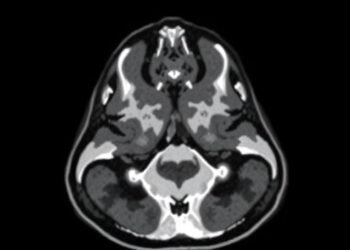

In a groundbreaking study set to redefine pediatric imaging recommendations, researchers have developed a locally deployed context-aware chatbot that significantly ...